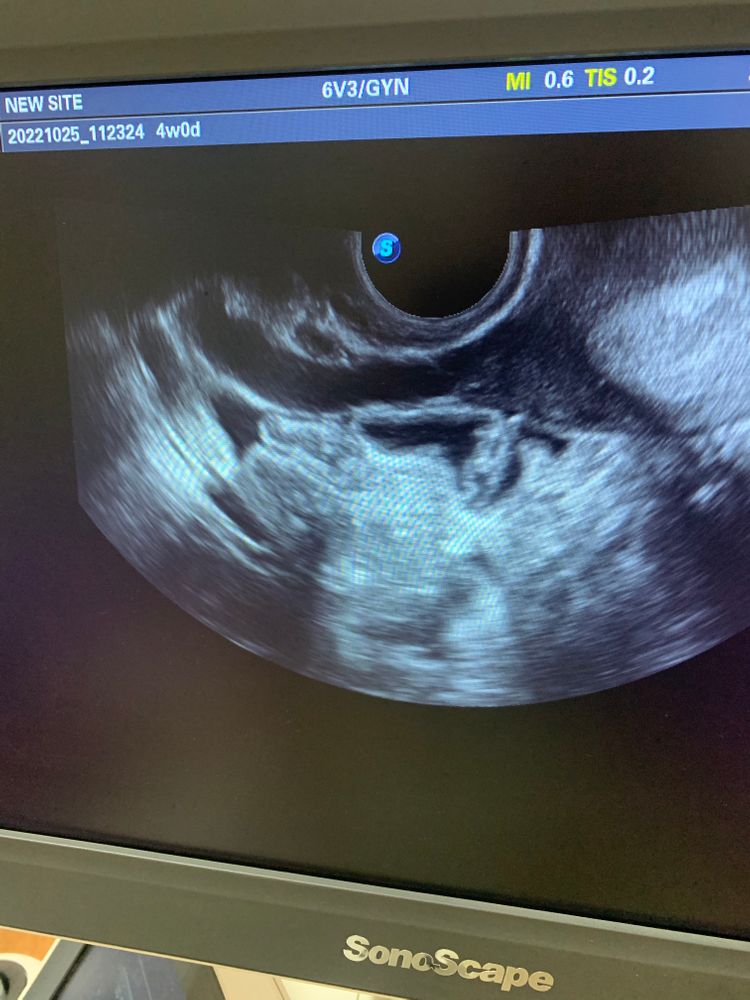

Труба или Вена ?

одна врач кричит труба ( гидрос) ,другие две , что Вена ... на что больше похоже ??может конечно так невозможно определить, но все же ...труба осталась у меня одна ...страшно

На УЗИ трубу и вену нельзя перепутать. При включении допплера кровоток будет виден во всем просвете вены. У трубы кровотока не будет. Странные сомнения у докторов. Может они сертификатом узи не владеют? Или первый раз гинекологически смотрят. И вообще гидросальпинкс выглядит иначе. Как извитая колбаска, накладываясь участками сама на себя. На фото изображение больше похоже на сосуд. Ровное и равномерно расширено.

У меня сильный варикоз вен таза, расширение более 7 мм (от 1 см уже оперируют). И знаешь, выглядят они не так 🤷♀️ похоже, труба все же.